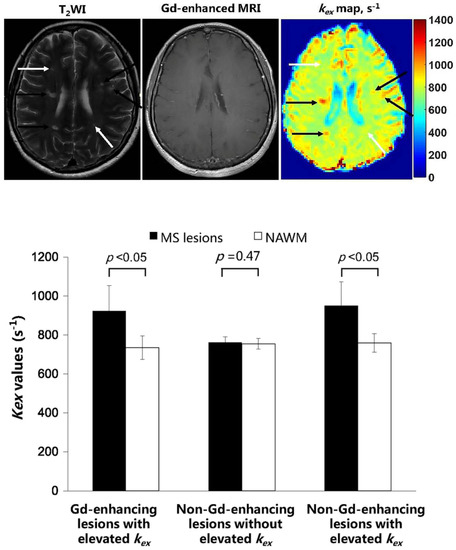

- Ye, H.; Shaghaghi, M.; Chen, Q.; Zhang, Y.; Lutz, S.E.; Chen, W.; Cai, K. In Vivo Proton Exchange Rate (kex) MRI for the Characterization of Multiple Sclerosis Lesions in Patients. J. Magn. Reson. Imaging 2020, 53, 408–415. [Google Scholar] [CrossRef]